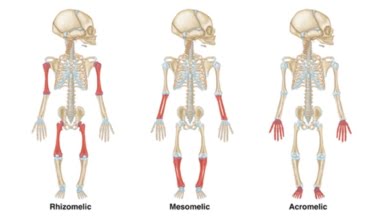

[Video] Loạn sản hệ xương, Bs Loan

Loạn sản hệ xương là bài giảng trong Khóa học Siêu âm Sản phụ khoa (BV Từ Dũ) do ThS Ngô Thị Kim Loan giảng dạy.